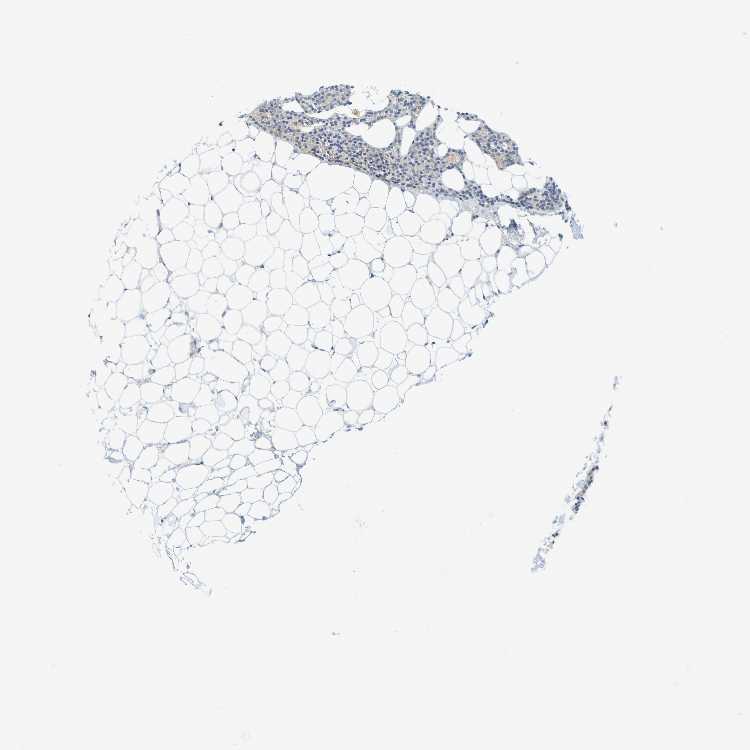

PARATHYROID GLAND - Antibody stainingi

Antibody staining in the annotated cell types in the current human tissue is reported as not detected, low, medium, or high, based on conventional immunohistochemistry profiling in selected tissues. This score is based on the combination of the staining intensity and fraction of stained cells.

Each image is clickable and will lead to virtual microscopy that enables deeper exploration of all samples and also displays staining intensity scores, fraction scores and subcellular localization as well as patient and tissue information for each sample.

Antibody HPA011138

Glandular cells Low